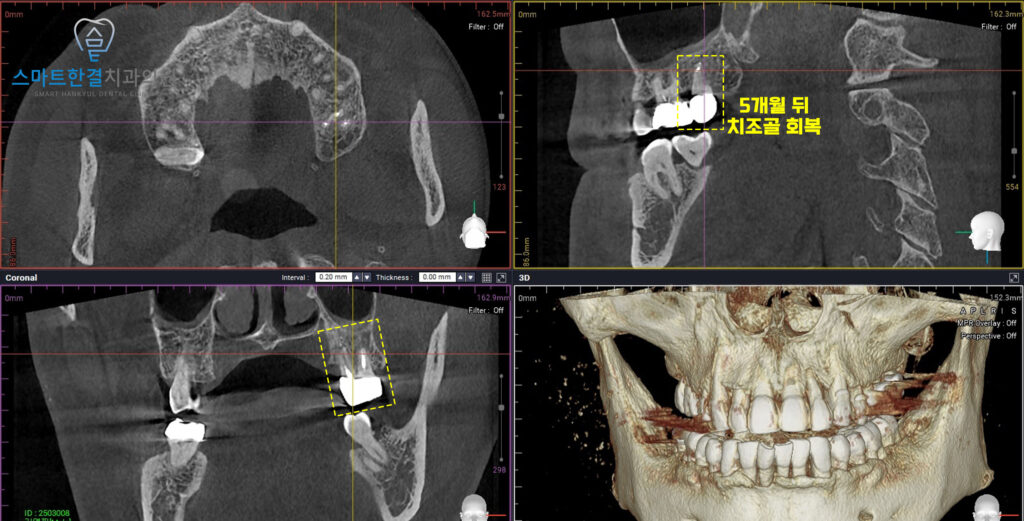

26.01

CT를 촬영하여 확인해 보았을 때도,

치아 뿌리 주변으로 치조골이

깨끗하게 회복되었으며

치아의 흔들림과 통증도 완전히 사라지셨답니다.

치료 과정은 성공적으로 마무리되었으며,

자연 치아를 보존할 수 있는

좋은 결과를 얻을 수 있었어요. (^^)

25.09 / 26.01

화서동치과 스마트한결치과의

신경치료 전후 사진이에요.